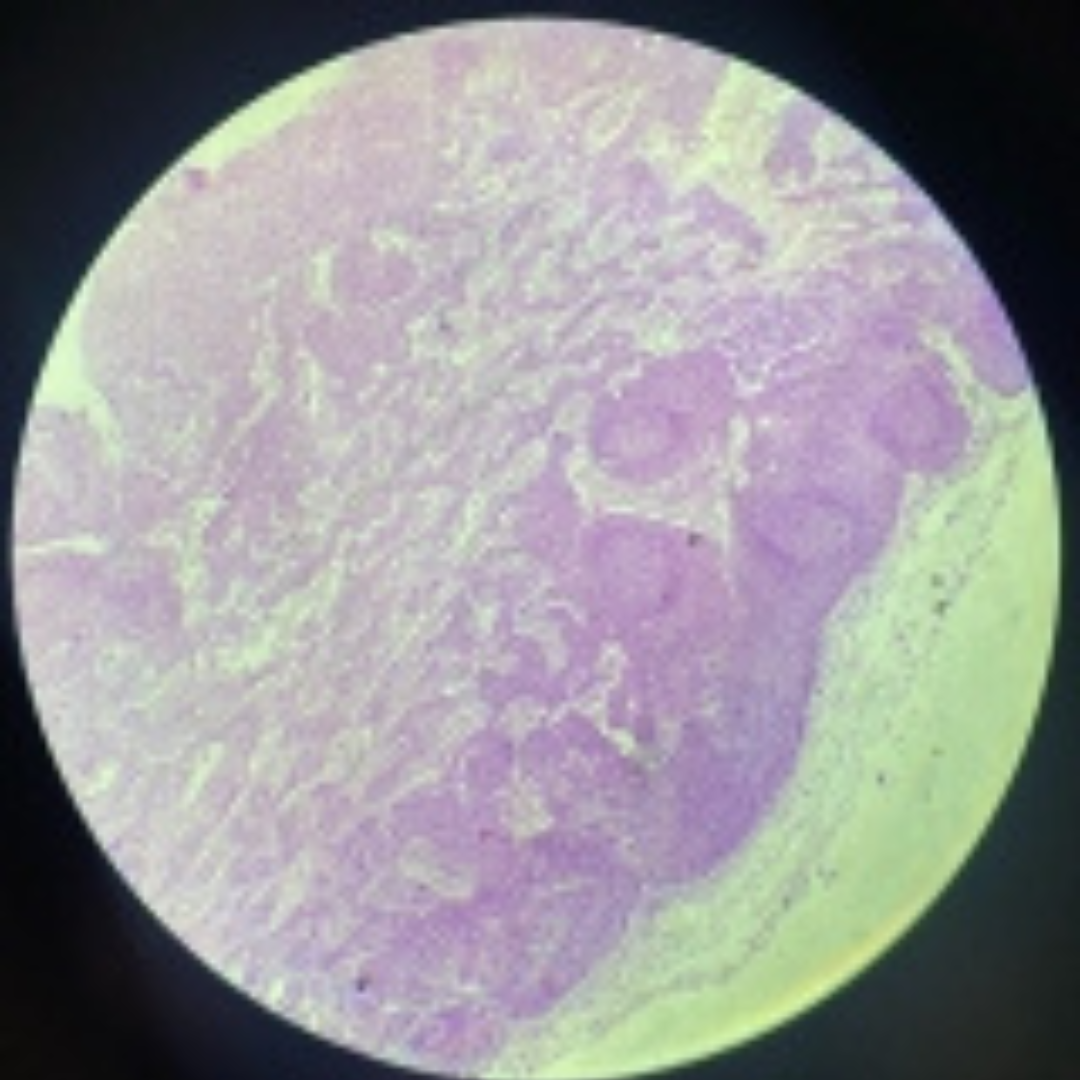

Thymus (Involuted)

30

New cards

Thymus (Involuted)

31

New cards

Thymus (Involuted)

32

New cards

Thymus

33

New cards

Thymus

34

New cards

Thymus

35

New cards

Thymus (Involuted)